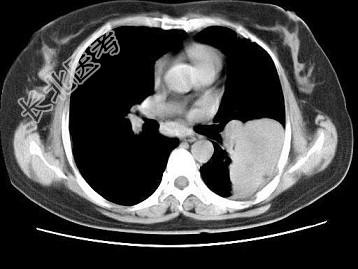

- 单项选择题女,52岁, 左侧背痛1月,胸部CT如图, 最可能的诊断为 ( )

A、左肺中央型肺癌

B、左肺周围型肺癌

C、左肺感染

D、左肺炎性假瘤

E、肺隔离征